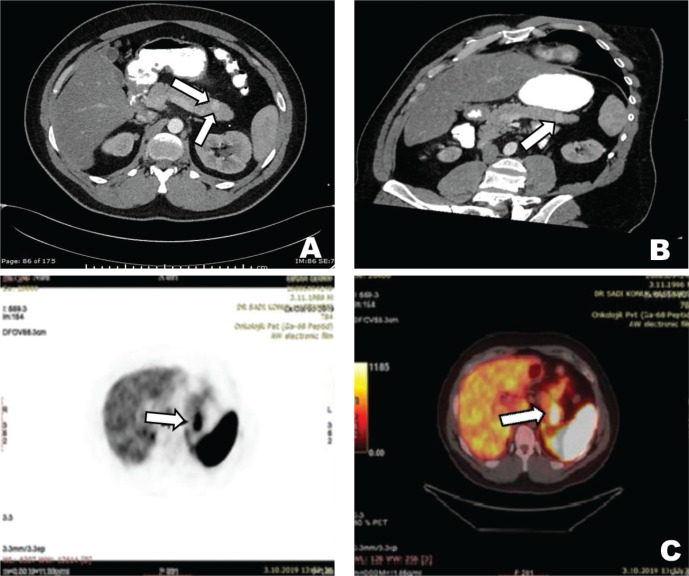

The main symptoms of the patient at admission were palpitations, diaphoresis, confusion, and these symptoms were improved with consuming sugary foods. The symptoms started about one year ago and have increased gradually during the last four months. The patient woke up nearly every night to consume sugary food and kept some sugary food with him wherever he went, especially during the last four months. There was no history of newly developed syncope or seizure. In the physical examination, the patient’s height was 168 cm, and the patient’s weight was 78 kg. He had angiofibromas on the face, trunk, and neck. His blood pressure and the other systems’ examination were normal. In laboratory examination, fasting glucose level was found to be 64 mg/dL and insulin level at 34 µIU/mL; other laboratory parameters were within normal limits (Table 1). Seventy-two hours fasting test was performed on the patient due to the symptoms of hypoglycemia. When the patient developed symptomatic hypoglycemia at the 8th hour of the test, a low glucose level at 41 mg/dL, a high insülin level at 21.65 µIU/mL, and a high C-peptide level at 7.04 ng/mL were found. The urine sulfonylurea screen test was negative. A lesion with a 12x7 mm size in the pancreatic tail and multiple lesions with fat densities in both kidneys were detected in the abdominal CT (Fig. 1). Increased uptake of Ga-68 DOTATATE (SUV max: 22.7) in the pancreatic tail was detected in Ga-68 PET-CT (gallium-68 positron emission tomography-computed tomography) (Fig. 1). The patient was diagnosed with insulinoma with clinical, laboratory, and imaging findings. As a result, the patient underwent a distal pancreatectomy. In pathological evaluation, there was no lymphovascular invasion, the mitotic rate was 1/10 at a high power field, and the Ki-67 index was low (%1). Chromogranin A and synaptophysin staining were positive, while vimentin and CD10 staining were negative. Immunohistochemical analysis confirmed a low-grade tumor of NETs consistent with an insulinoma (Fig. 2). Unfortunately, insulin staining was not routinely available at our institution, so it was not performed. The patient’s symptoms improved postoperatively. The follow-up of the patient in our clinic is ongoing during the 2-year period after the operation, and the symptoms of hypoglycemia were not observed in our patient.

Figure 1.

12x7 mm hypervascular solid lesion with increased enhancement in the tail of the pancreas in axial CT images (A), hypervascular solid lesion in the tail of the pancreas in arterial phase multiplanar reformation CT images (B), and focal increased Ga-68 DOTATATE uptake in the tail of the pancreas (suvMAX: 22.78) (C).